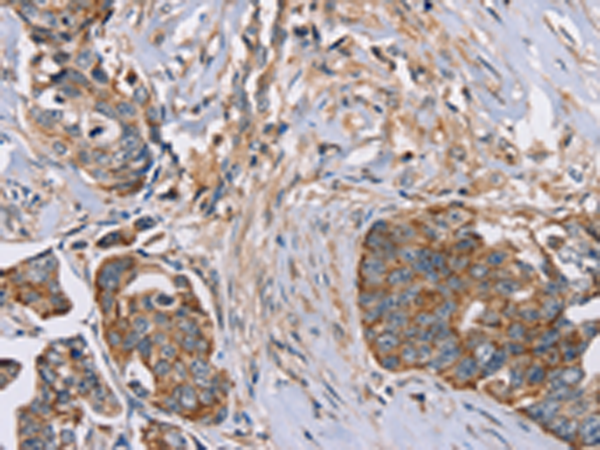

分类: 科研抗体货号: P08294别名: ET1; PPET1; HDLCQ7应用: IHC反应种属: Human

分类: 科研抗体货号: P08307别名: PKB; PTK; CAKB; FAK2; PYK2; CADTK; FADK2; RAFTK应用: WB,IHC反应种属: Human, Mouse, Rat

分类: 科研抗体货号: P08313别名: FAPA; SIMP; DPPIV; FAPalpha应用: WB,IHC反应种属: Human, Mouse